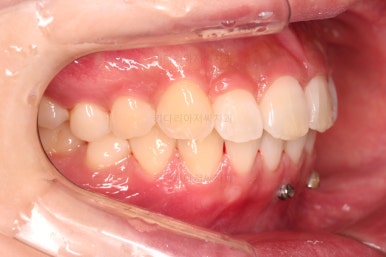

1. 초진

초진 시 입안의 모습입니다.

어금니 쪽은 약간 삐뚤긴 하지만 꼭 교정해야 할 정도는 아니고, 불편감 없이 비교적 잘 맞물리는 상태였습니다.

다만, 앞니ㅉㄱ이 공간이 부족해서 중간 치아들이 많이 회전되어있는데, 이를 환자분들의 표현에 따르면 "나비치아" 라고 부릅니다.

위아래 중간 앞니가 모두 나비치아처럼 되어있고요.

윗니가 아랫니보다 앞쪽으로 나와 있는 모습에 아래앞니가 윗니쪽으로 깊숙이 올라간 "과개교합" 양상을 보였습니다.